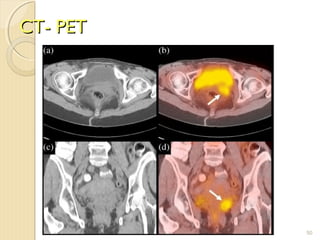

Positron emission tomography (PET) scan

For a PET scan, a form of radioactive sugar (known as fluorodeoxyglucose or FDG) is injected

into the blood. The amount of radioactivity used is very low. Cancer cells in the body grow

rapidly, so they absorb large amounts of the radioactive sugar. After about an hour, you will be

moved onto a table in the PET scanner. You lie on the table for about 30 minutes while a special

camera creates a picture of areas of radioactivity in the body. The picture is not finely detailed

like a CT or MRI scan, but it provides helpful information about your whole body.

A PET scan can help give the doctor a better idea of whether an abnormal area seen on another

imaging test is a tumor or not. If you have already been diagnosed with cancer, your doctor may

use this test to see if the cancer has spread to lymph nodes or other parts of the body. A PET scan

can also be useful if your doctor thinks the cancer may have spread but doesn't know where.

Special machines are able to perform both a PET and CT scan at the same time (PET/CT scan).

This allows the doctor to compare areas of higher radioactivity on the PET with the more detailed

picture of that area on the CT.

CT- PETCT- PET